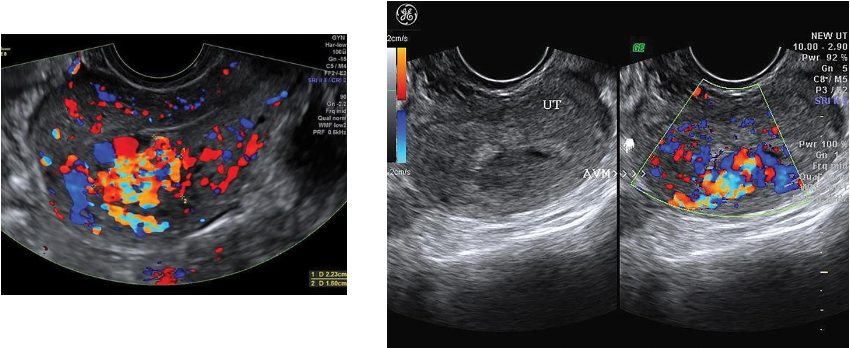

-consist of vascular plexus of arteries and veins

without intervening capillary network.

Rare; usually involving myometrium and rarely endometrium

Congenital or teratogenic (acquired) due to pelvic trauma, surgery, or gestational

trophoblastic neoplasia

Clinically, women of childbearing years have metrorrhagia with blood loss and anemia.

Diagnosis critical because dilation and curettage may lead to catastrophic hemorrhaging

Sonographic findings

Sonographically, serpiginous, anechoic structures seen within the pelvis

Uterine AVMs may appear as subtle myometrial inhomogeneity, tubular spaces within myometrium,

intramural uterine mass, endometrial or cervical mass

Color Doppler diagnostic to show blood flow within anechoic structures

May be florid-colored mosaic pattern with apparent flow reversals and

areas of color aliasing

Spectral Doppler shows high-velocity, low-resistance arterial flow

coupled with high-velocity venous flow with arterial component.

Arteriovenous Malformations